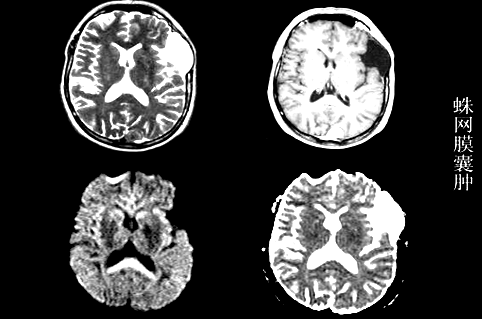

3、胆脂瘤与蛛网膜囊肿鉴别:胆脂瘤含大量肌固醇晶体和脂肪会限制水分了的弥散运动,从而DWI为高信号,ADC为低信号;蛛网膜囊肿含脑脊液样液体,弥散不受限,从而DWI为低信号,ADC为高信号;